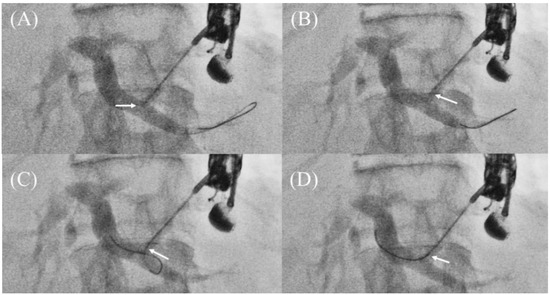

- Ueno, S.; Ogura, T.; Higuchi, K. Moving scope technique for guidewire insertion during endoscopic ultrasound-guided hepaticogastrostomy. Dig. Endosc. 2021, 33, e109–e110. [Google Scholar] [CrossRef]

- Ogura, T.; Masuda, D.; Takeuchi, T.; Fukunishi, S.; Higuchi, K. Liver impaction technique to prevent shearing of the guidewire during endoscopic ultrasound-guided hepaticogastrostomy. Endoscopy 2015, 47, E583–E584. [Google Scholar] [CrossRef]